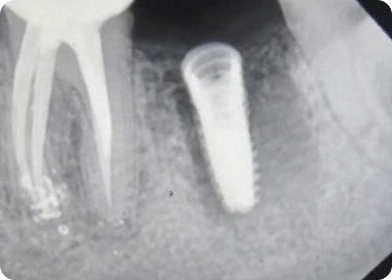

Flapless Surgery with Nidaan UniGuide

How precision-guided implantology reduced recovery times.

Post-Operative

Multi-Implant Planning Accuracy

Improved surgical outcomes for a complex dental restoration.

Predictive Implantology with Digital Workflow

Seamless integration of CBCT + intraoral scan data.